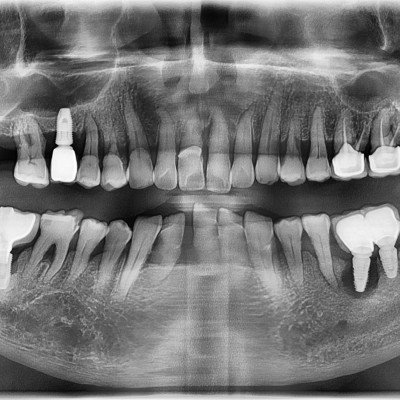

임플란트 재수술 타원임플란트 #14 파절되어 재수술

작성자 이턱이 작성일 01-27 조회 105